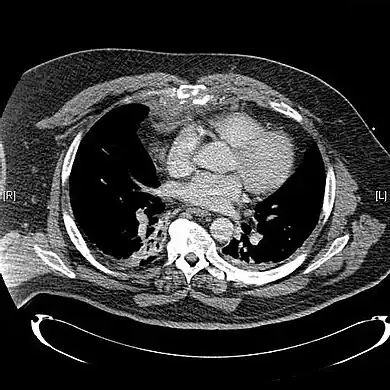

Computed tomography identifying displaced sternal fracture. -

CT scan showing a comminuted sternal fracture.[14]